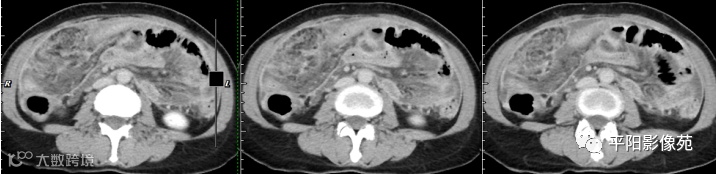

腹部增强 门脉期